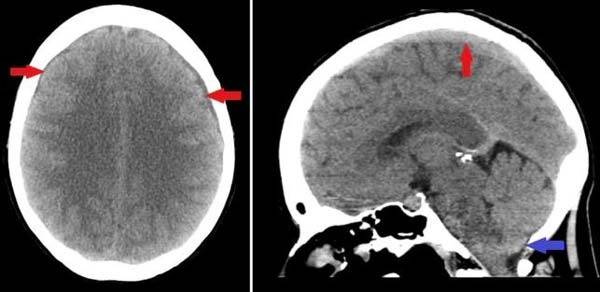

영국 킹스 칼리지대 의대 병원 의료진에 따르면 영국의 40대 여성 A씨는 필라테스를 하면서 목을 젖히고 머리를 뒤로 눕히는 자세를 취했다. 이때 왼쪽 목에서 ‘펑’하는 소리가 난 후 두통을 느꼈다. 그 후 며칠 동안 두통이 지속됐고 병원을 찾아 물리치료를 받았다. 하지만 두통은 4주 동안 계속돼 A씨는 더 큰 병원을 찾아 CT(컴퓨터 단층 촬영)와 MRI(자기 공명 영상) 검사를 받았다. 그 결과, 뇌척수액(뇌와 척수를 보호하고 순환을 돕는 맑은 액체)이 누출돼 고여 있는 것이 확인됐다. 의료진은 “목을 젖히는 자세를 하면서 척수가 압박받아 경막이 파열돼 뇌척수액이 샌 것 같다”며 “뇌척수액 누출과 축적으로 인해 두통이 발생할 수 있으며, 이 두통은 똑바로 앉아 있을 때 더 심해진다”고 말했다. A씨는 병원에 입원해 ‘절대 침상 안정’과 ‘카페인 복용’ 치료를 받았다. 절대 침상 안정은 휴식 치료라고도 하며, 주로 침대에 누워서 보내는 의료 치료법이다. 또한 카페인은 뇌척수액 생성을 증가시키고, 혈관을 수축시켜 뇌 혈류를 감소시켜 두통 완화에 효과적이다. A씨는 2주 동안 치료받은 뒤 퇴원했다. 한 달 후 추적관찰에서 A씨 상태는 정상으로 나타났다. 의료진은 “필라테스 자세와 뇌척수액 누출의 연관성에 관한 최초의 사례다”며 “이런 부상이 드물긴 하지만, 필라테스 자세를 취할 때 주의를 기울여야 한다”고 말했다.

뇌척수액 누출을 진단하기 위해선 먼저 CT나 MRI 촬영을 통해 뇌척수액이 고여있는지 확인한다. 또한 ▲뇌압이 60mmHg 이하인지 측정하고 ▲뇌척수액이 외부로 누출되는 것을 확인하는 뇌조영술과 ▲뇌척수액 누출 부위를 확인하는 척수조영술을 시행한다.